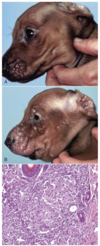

Melanoma

Dog, Horse, Angora Goat

Usually dark brown

Location, size, mitotic index, and cell morphology may help predict behavior